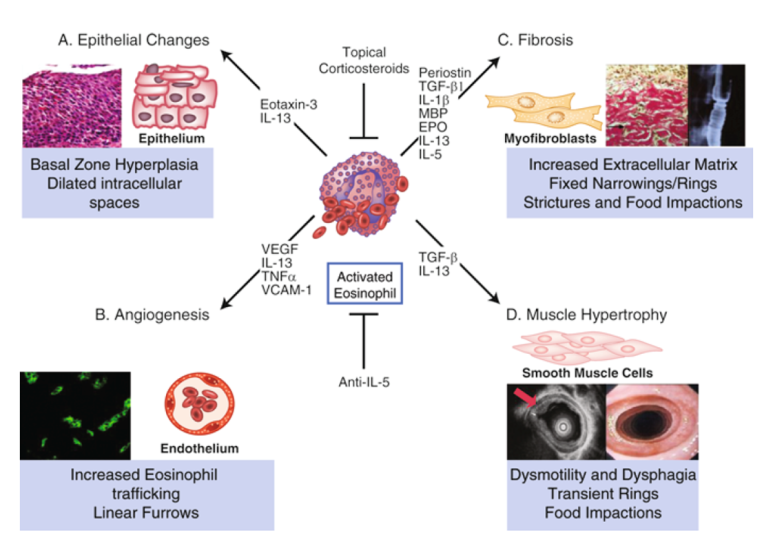

현재 명확하게 제시된 메커니즘은 없지만 nature에 발표된 리뷰에 따르면 산 노출로 식도의 epithelial barier injury가 발생하면 해당 부위에 음식, aeroallergen이 epithelial barrier를 가로질러 식도 내로 들어가게 됩니다. 이렇게 들어간 외부 allergen은 면역세포(Th2 cell, Mast cell, 호산구 등)에 의해 염증반응이 증가합니다.

이 염증반응에 의해 혈관의 신생합성이 증가하여 근육층이 두꺼워지고 섬유화가 진행되어 식도의 운동성을 저하시키고 내강이 좁아지는 담보이기 때문에 음식통과를 위한 경로가 적어집니다.

경과기 전에 말씀드렸다시피 먼저 호산구 식도염의 초기 증상은 염증 반응입니다. 이 염증 반응은 치료하지 않을 경우 esophageal remodling을 통해 내강이 좁아지고 기능 저하가 발생합니다. 하지만 항염증 요법을 시행할 경우, 호산구 식도염 질병의 진행 결과를 제한할 수 있다는 일부 보고가 발표되었습니다.이를 바탕으로 질병 발생 초기 또는 소아 청소년에서 발생한 호산구 식도염의 경우 약물치료 또는 식사치료를 할 수 있으나 이미 병변이 진행 중이고 섬유화가 진행된 경우 식도확장시술 외에는 다른 약물, 식생활료요법이 효과적이지 않습니다.